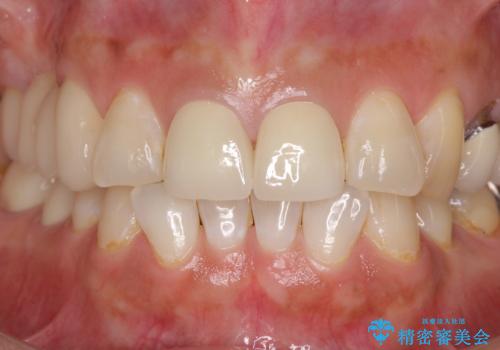

前歯2本を同時に処置したことにより、色合いも形態もバランスの取れた仕上がりとすることができました。

10年近く人にあまり見られないようにしていた前歯でしたが、人目を気にせず笑えるようになり、患者様には大変満足していただきました。